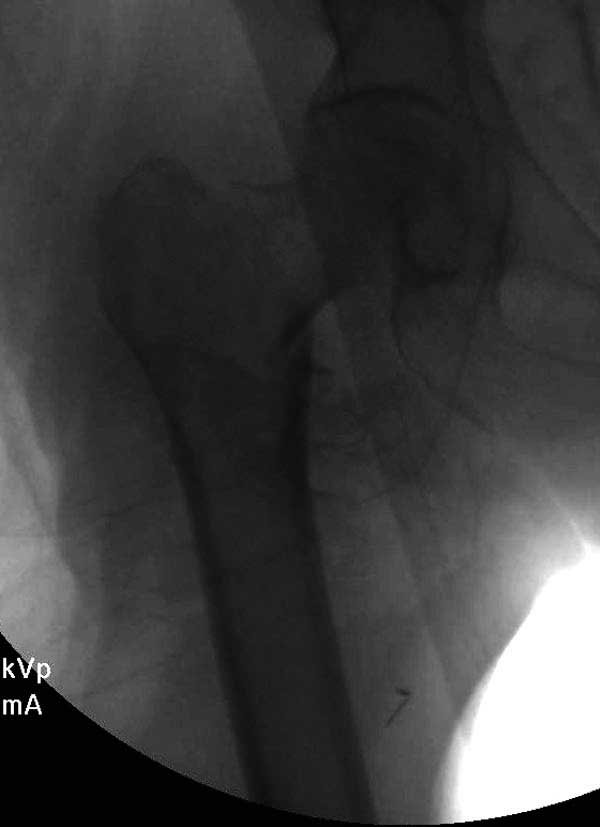

Вторая операция- это фаза сохранения головки бедра. Желательно приложить все усилия и сохранить головку, но, как видно, “фиаско” продолжается. Здесь вместо нейтрализации сил между медиальной и латеральными сторонами была попытка удержать варус. Варус не удержать ни деротационными шурупами о котором говорили и не костными стружками вбитые в шейку, потому что вся нагрузка упирается в головку.

Как отметил Евгений, 95 degree Blade Plate Fixed Angle device  расчитана на восстановление взаимоотношении между головкой и диафизом, а все остальные фиксаторы (Gamma, Afifuxus и др.) работают за счет нагрузки в верхнем полюсе головки. Верхний полюс успели разрушить, и в головке единственное место, который смог бы удержать широкий клинок конструкции, это медиально-низкий сегмент. После установки клинка засчет дистракции можно удлинить конечность на 15мм, а добавленный в дефект ауто-графт закончил бы дело.